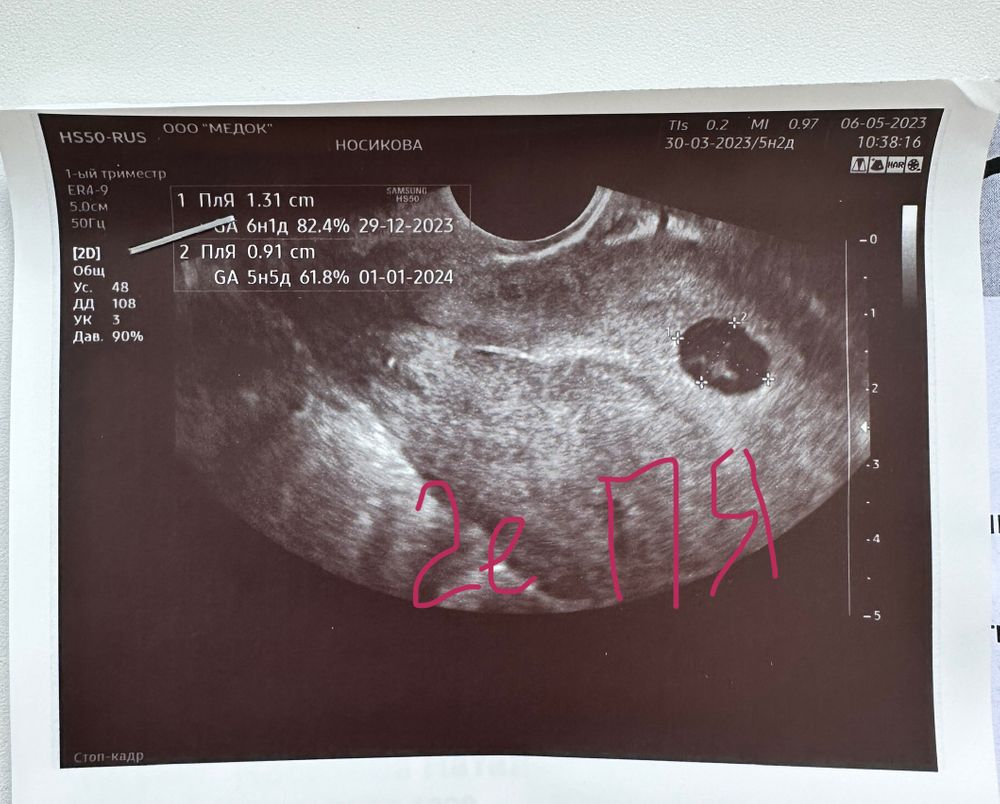

Сходила на 1 УЗИ, узист не понимает, что это 🙈

Ну вообще УЗИ написано коряво как-то. Не может в ПЯ 5 мм уже быть желточный мешок да еще и на половину размера плодного яйца. 11 больше похоже на правду. Да и там может быть рано для желточного. В любом случае сейчас ничего не понять, надо в динамике смотреть через недельку. Природе нужно время на рост и развитие. Там и ситуация прояснится

Привет!) Поздравляю! Ну это же Медок. Я не удивлена, что они не понимают.. Сходи в место посерьезнее. Почему свд 5 мм это 5и2 нед, а свд 11 мм это 5и0 нед😅11 это же больше 5. Вообще по картинке оба пя не пустые. Если второе это тоже пя

Ромашка, привет)) Записалась к Пятых через неделю, уж там виднее будет) Я думаю, она опечаталась про второе СВД, вместо 6 недель написала 5 😅 Она минут 10 заключение печатала, ждали под кабинетом.

Дарья , это да, повторю через недельку, конечно. Просто странно, что узист не внес никакой ясности 😅 Почему двойня, если 1 желтое тело..